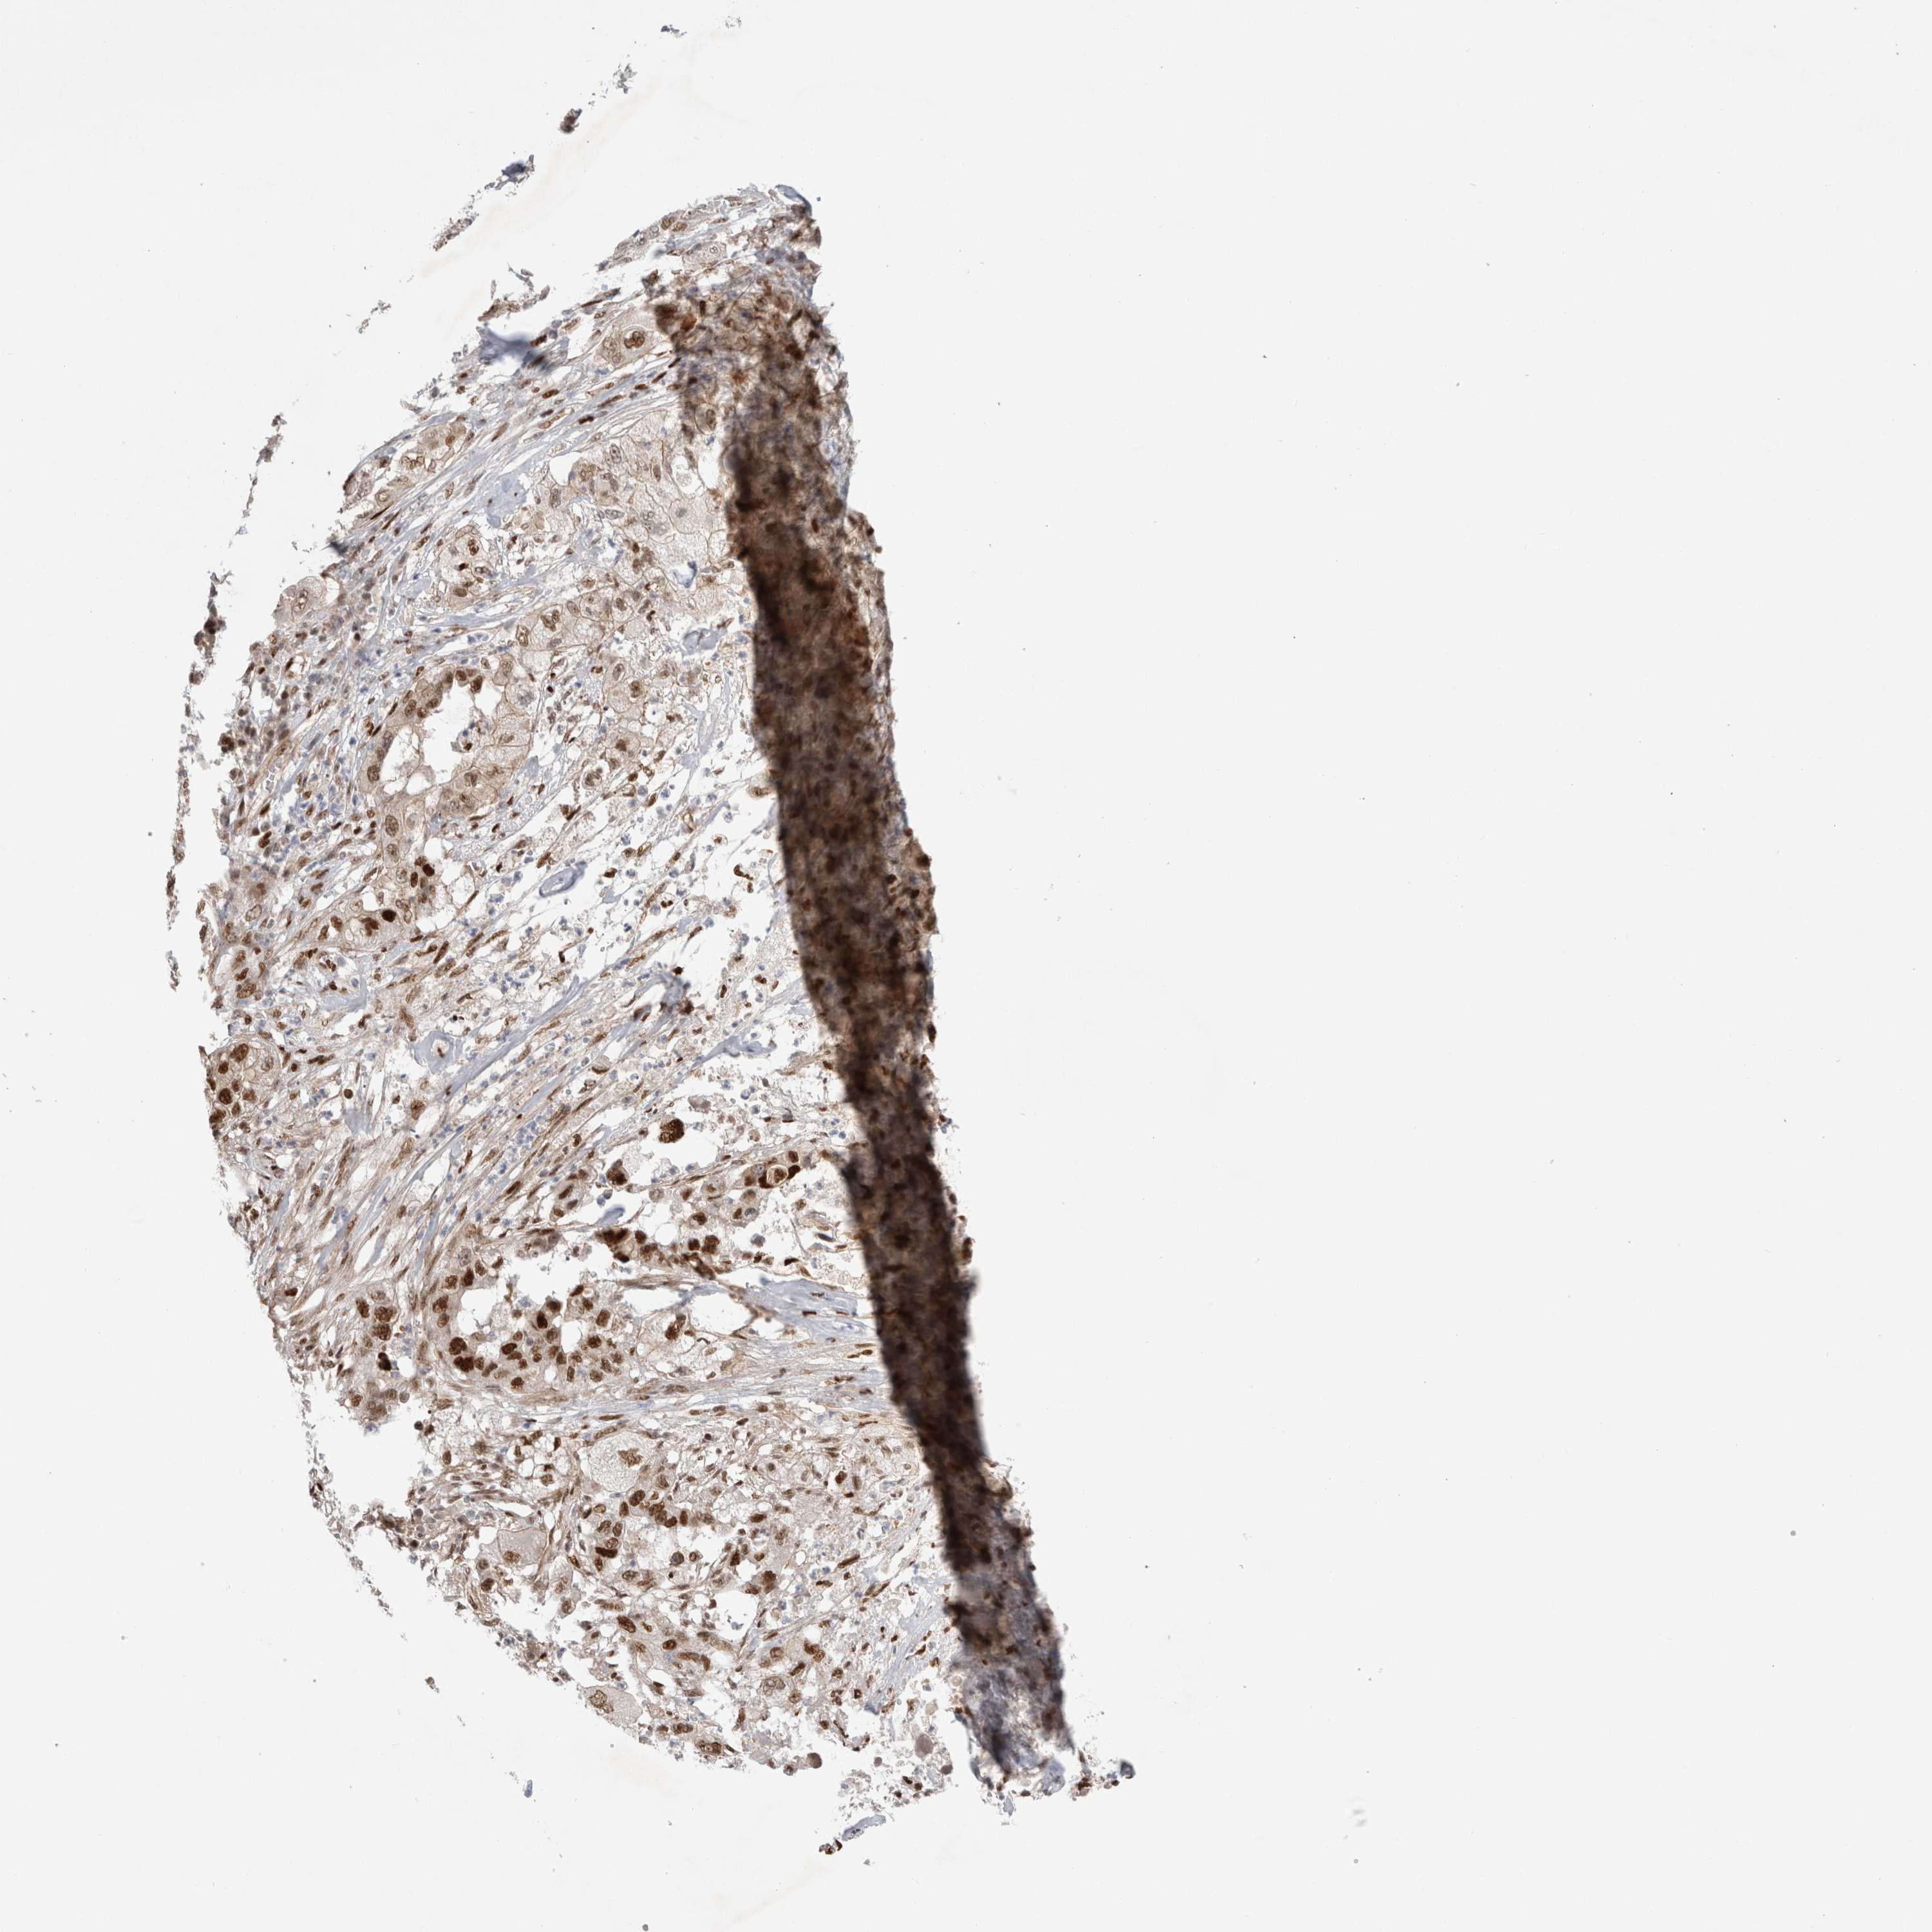

PANCREATIC CANCER - Protein expressioni

A mouse-over function shows sample information and annotation data. Click on an image to view it in a full screen mode. Samples can be filtered based on level of antibody staining by selecting one or several of the following categories: high, medium, low and not detected. The assay and annotation is described here.

Note that samples used for immunohistochemistry by the Human Protein Atlas do not correspond to samples in the TCGA dataset.

Antibody stainingi

Antibody staining in the annotated cell types in the current human tissue is reported as not detected, low, medium, or high, based on conventional immunohistochemistry profiling in selected tissues. This score is based on the combination of the staining intensity and fraction of stained cells.

Each image is clickable and will lead to virtual microscopy that enables deeper exploration of all samples and also displays staining intensity scores, fraction scores and subcellular localization as well as patient and tissue information for each sample.

Antibody HPA025958

Antibody CAB020722

Staining

High

Medium

Low

Not detected

Intensity

Strong

Moderate

Weak

Negative

Quantity

>75%

75%-25%

<25%

None

Location

Nuclear

Cytoplasmic/membranous

Cytoplasmic/membranous,nuclear

Adenocarcinoma, NOS

Adenocarcinoma, metastatic, NOS